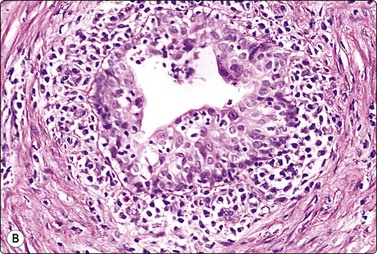

image image

Fig. 13.50 Uterine leiomyosarcoma

(A) Epithelioid pattern; dispersed, pleomorphic malignant cells of predominantly rounded shape, pale fragile cytoplasm (MGG, HP); (B) Corresponding tissue section; note abnormal mitotic figure (H&E, IP).

FNA smears of endometrial stromal sarcoma are highly cellular.123,124 The cells are plump spindled, eosinophilic with anastomosing cytoplasmic processes. In low-grade tumors (endolymphatic stromal myosis), the cells are relatively small and uniform with bland nuclei, and form cohesive clusters. In high-grade tumors, cells are mainly dispersed and there is no architectural pattern. Nuclei are oval, vesicular, enlarged and moderately pleomorphic, with granular chromatin and small nucleoli. Mitotic figures are frequently observed (Fig. 13.51). Positive staining for CD10 is helpful in the distinction from other spindle cell lesions.

Fig. 13.51 Endometrial stromal sarcoma

(A) Poorly cohesive plump spindle cells with pale ovoid nuclei and small nucleoli; note anastomosing strands of eosinophilic cytoplasm and a few mitoses (H&E, IP); (B) Corresponding tissue section (H&E, IP).